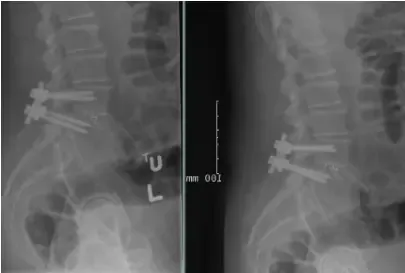

Patient underwent decompression laminectomy with decompression of nerve roots and transforaminal interbody fusion using PEEK (polyether ether ketone) cage and pedicle screw and rod fixation for fusion at L4-5 level.

Fusion was achieved in about 3 months and patient was asymptomatic.